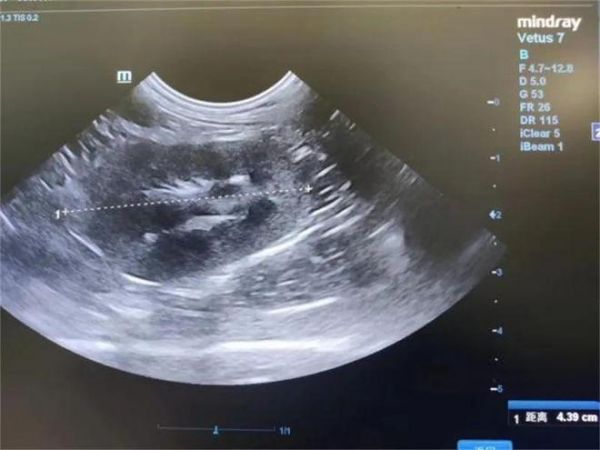

1.3.5 超声

肾皮质回声不均,肾轻度增大。胆汁淤积,可探及左心房轻度扩张,瓣膜增厚,重度脱垂,重度返流,可探及心室壁烟雾征,主动脉返流,心率不齐,瓣膜增厚,较厚处直径约0.8cm。